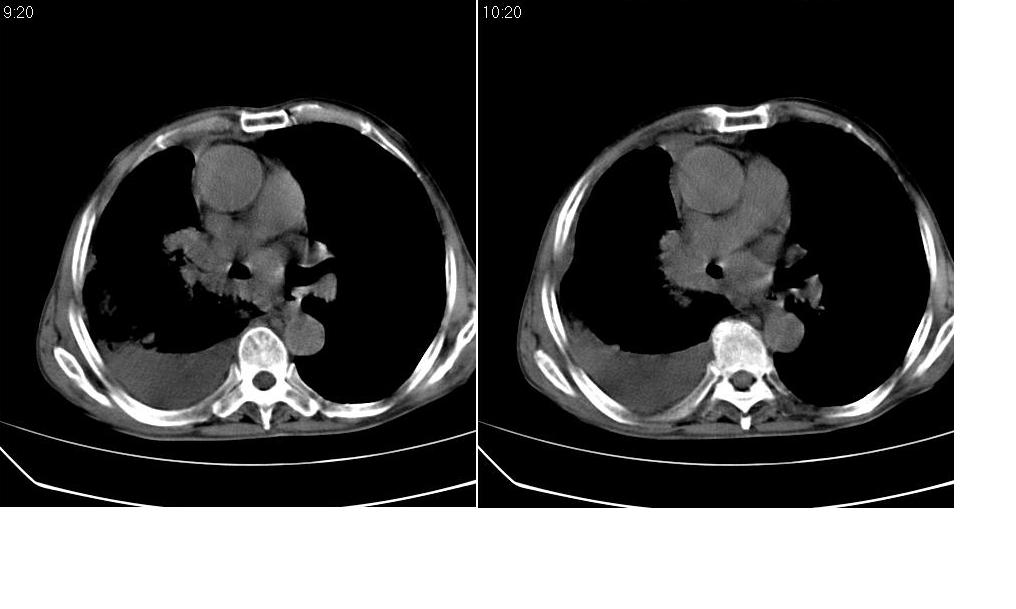

以下是引用zsl6918在2008-5-3 19:53:00的发言:[br]右肺中心型肺癌并纵隔淋巴结转移,胸膜转移,右肺癌性淋巴管炎。

以下是引用liuyue在2008-5-3 20:49:00的发言:[br]1.右侧中心型肺癌伴双肺转移瘤、纵隔淋巴结转移、右侧胸腔积液(侵及胸膜所致可能性大)。[br]2.右肺阻塞性肺炎,癌性淋巴管炎不除外。

以下是引用mzh123在2008-5-3 21:12:00的发言:[br]本人持有不同观点[br]1、右肺似有团块表现,但只有一个层面,所以本人认为还是以片为主,所以不能首先考虑肿瘤[br]2、右肺普遍成纤维化改变 并伴有片状炎症改变,和癌性淋巴管炎表现不同[br]3、所以本人认为是间质纤维化伴感染可能大 及胸腔积液